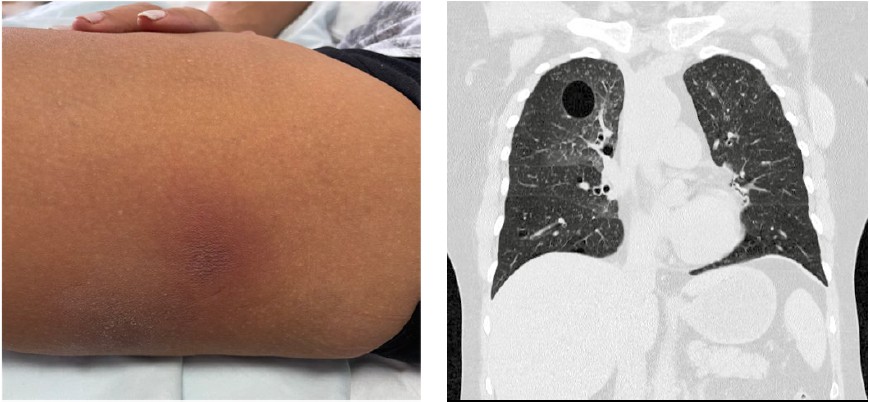

Mujer de 56 años con diagnóstico de lupus eritematoso sistémico (LES) en tratamiento inmunosupresor con micofenolato mofetilo y metilprednisolona oral, quien consultó por un cuadro clínico de siete meses de evolución caracterizado por epistaxis, asociado a perforación del septo nasal; posteriormente, asociado a disnea y poliartralgias. Tres meses después refiere presencia de placas eritematosas, edematosas, dolorosas y mal definidas en el muslo derecho (Figura 1, izquierda).

Al inicio es evaluada por el servicio de reumatología, en donde se sospecha una posible exacerbación del LES, con una puntuación de SLEDAI de 8. Los estudios paraclínicos iniciales revelaron niveles normales de complemento, anticuerpos anti-DNA negativos y un citoquímico urinario sin hematuria ni proteinuria. Ante la sospecha de compromiso pulmonar, se realizó una tomografía de alta resolución (TACAR) la cual evidenció múltiples lesiones quísticas en el parénquima pulmonar, asociado a nivel hidroaéreo en la lesión quística dominante del pulmón derecho, sugiriendo una neumonía intersticial linfocítica (Figura 1, derecha).